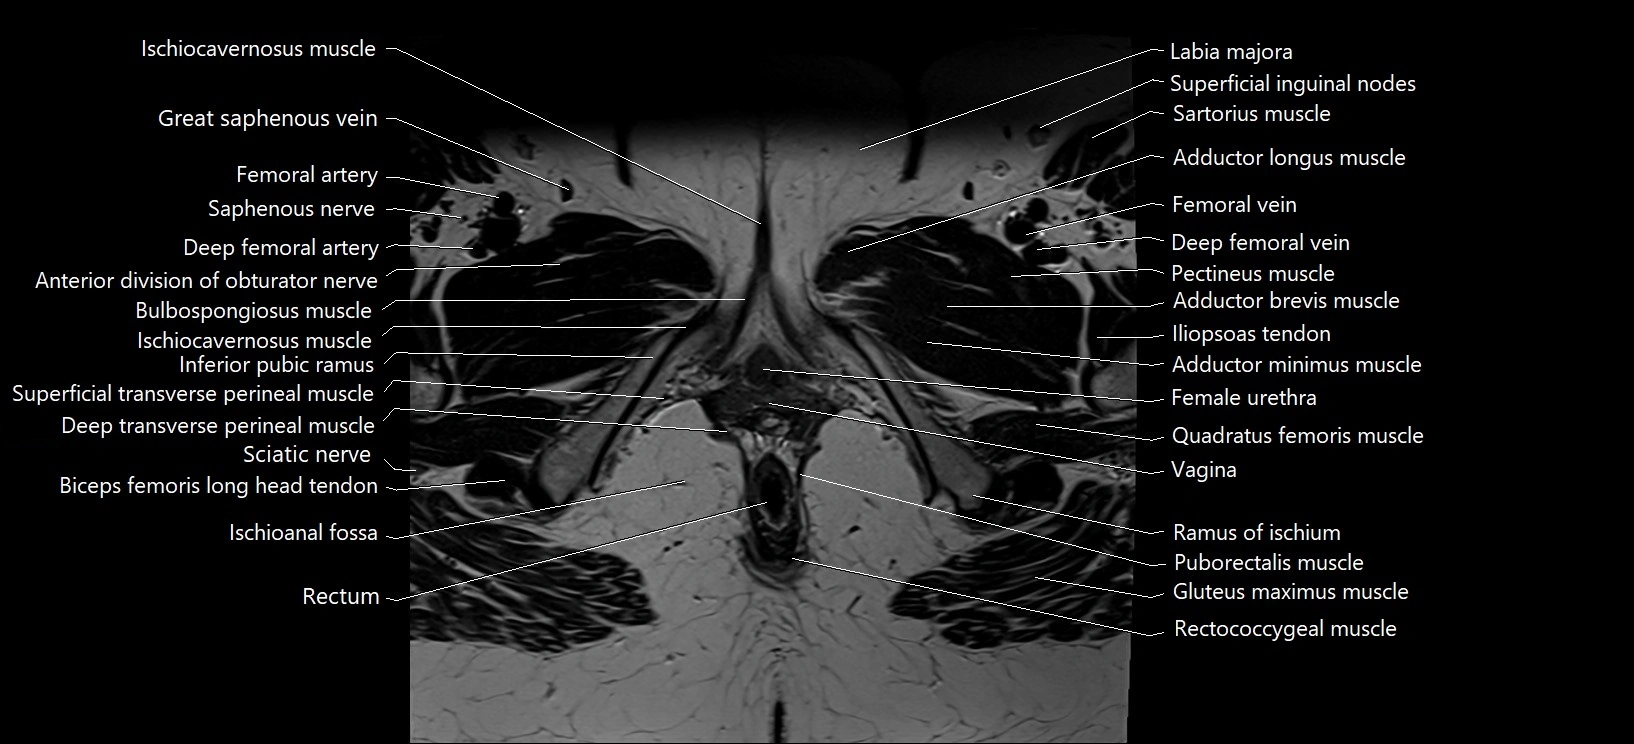

- Bulbospongiosus muscle (Female)

- Deep femoral artery (profunda femoris)

- Deep femoral vein (profunda femoris vein)

- Deep transverse perineal muscle

- Female urethra

- Femoral artery

- Femoral vein

- Gracilis muscle

- Iliopsoas tendon

- Inferior pubic ramus

- Ischioanal fossa

- Ischiocavernosus muscle (Female)

- Labia majora

- Pectineus muscle

- Posterior division of obturator nerve (Posterior branch of obturator nerve)

- Pudendal nerve

- Ramus of ischium

- Rectococcygeal muscle

- Rectum

- Saphenous nerve

- Sartorius muscle

- Sciatic nerve

- Superficial transverse perineal muscle

- Vagina